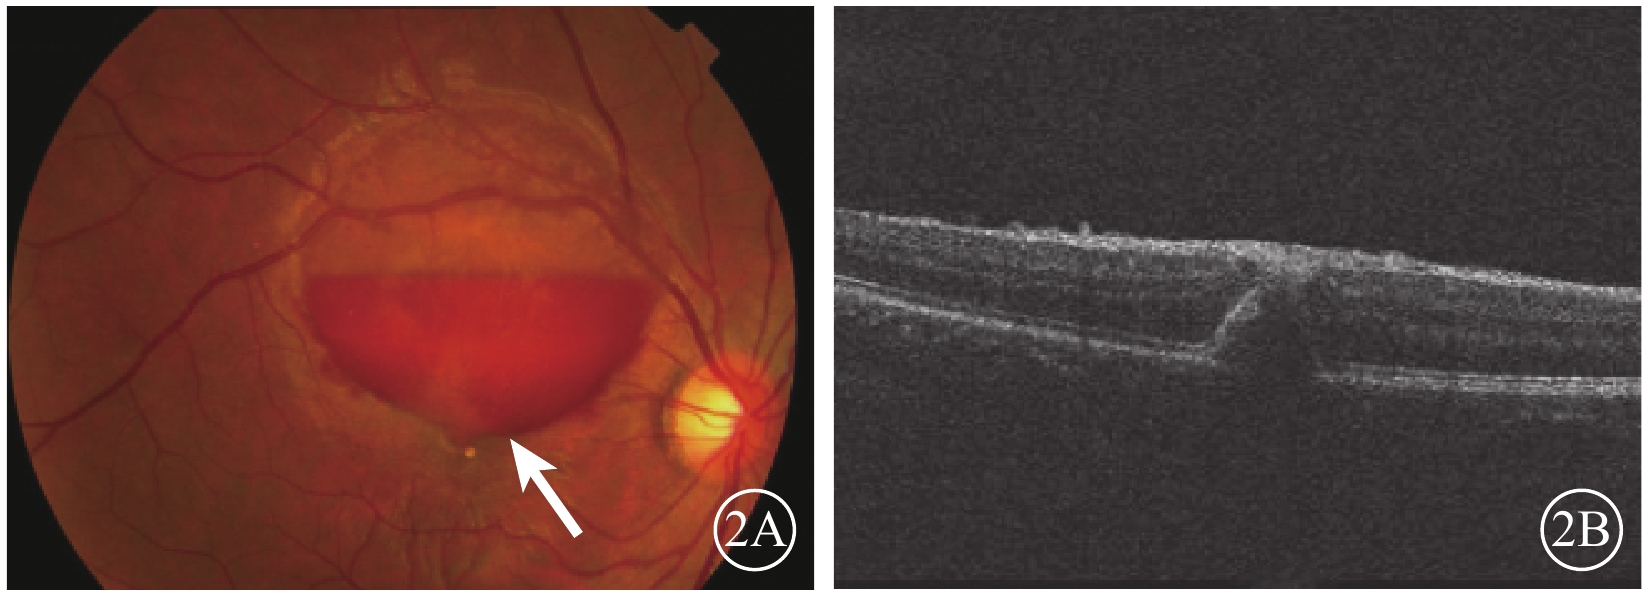

2015年12月7日行摻釹釔鋁石榴石(Nd:YAG)激光積血區內界膜(ILM)切開,最大能量3.5 mJ,單脈沖爆破模式,未見新鮮血液流出。未進行治療觀察。2016年1月27日復查,下方積血吸收邊緣至黃斑區(圖2A)。OCT檢查,黃斑區前ILM增厚,牽拉黃斑中心凹,黃斑正常結構消失(圖2B)。2月23日復查,右眼矯正視力0.25。黃斑區視網膜前出血基本吸收。OCT檢查,黃斑區ILM增厚,可見黃斑板層裂孔(圖3A)。4月20日復查OCT,黃斑中心凹處ILM增厚,中心凹鼻側ILM與其下視網膜組織分離,可見黃斑板層裂孔。仍未治療繼續觀察。8月17日復查,患者訴視物有水波紋樣浮動。OCT檢查,病變處ILM與其下視網膜組織分離,黃斑板層裂孔,黃斑中心凹處ILM較前略增厚(圖3B)。FFA檢查,黃斑拱環縮小,視網膜毛細血管變形稍紆曲,未見熒光素滲漏,可見線狀遮蔽熒光。

圖2

右眼彩色眼底、OCT像。2A. 彩色眼底像,積血較前吸收,下方邊緣至黃斑區(白箭);2B. OCT像,黃斑區ILM增厚,牽拉黃斑中心凹

圖2

右眼彩色眼底、OCT像。2A. 彩色眼底像,積血較前吸收,下方邊緣至黃斑區(白箭);2B. OCT像,黃斑區ILM增厚,牽拉黃斑中心凹

2015年12月7日行摻釹釔鋁石榴石(Nd:YAG)激光積血區內界膜(ILM)切開,最大能量3.5 mJ,單脈沖爆破模式,未見新鮮血液流出。未進行治療觀察。2016年1月27日復查,下方積血吸收邊緣至黃斑區(圖2A)。OCT檢查,黃斑區前ILM增厚,牽拉黃斑中心凹,黃斑正常結構消失(圖2B)。2月23日復查,右眼矯正視力0.25。黃斑區視網膜前出血基本吸收。OCT檢查,黃斑區ILM增厚,可見黃斑板層裂孔(圖3A)。4月20日復查OCT,黃斑中心凹處ILM增厚,中心凹鼻側ILM與其下視網膜組織分離,可見黃斑板層裂孔。仍未治療繼續觀察。8月17日復查,患者訴視物有水波紋樣浮動。OCT檢查,病變處ILM與其下視網膜組織分離,黃斑板層裂孔,黃斑中心凹處ILM較前略增厚(圖3B)。FFA檢查,黃斑拱環縮小,視網膜毛細血管變形稍紆曲,未見熒光素滲漏,可見線狀遮蔽熒光。

圖2

右眼彩色眼底、OCT像。2A. 彩色眼底像,積血較前吸收,下方邊緣至黃斑區(白箭);2B. OCT像,黃斑區ILM增厚,牽拉黃斑中心凹

圖2

右眼彩色眼底、OCT像。2A. 彩色眼底像,積血較前吸收,下方邊緣至黃斑區(白箭);2B. OCT像,黃斑區ILM增厚,牽拉黃斑中心凹